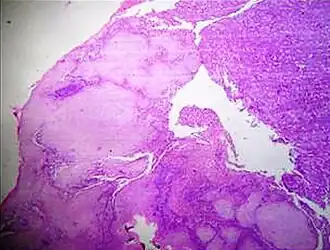

In microscopy, an artifact is an apparent structural detail that is caused by the processing of the specimen and is thus not a legitimate feature of the specimen. In light microscopy, artifacts may be produced by air bubbles trapped under the slide's cover slip.[1]

A crush artifact is an artificial elongation and distortion seen in histopathology and cytopathology studies, presumably because of iatrogenic compression of tissues. Distortion can be caused by the slightest compression of tissue and can provide difficulties in diagnosis.[2][3] It may cause chromatin to be squeezed out of nuclei.[4] Inflammatory and tumor cells are most susceptible to crush artifacts.[4]

Cellulose contamination, in H&E stain and polarized light

Cardiac muscle (bottom) with contamination from thyroid tissue (center)